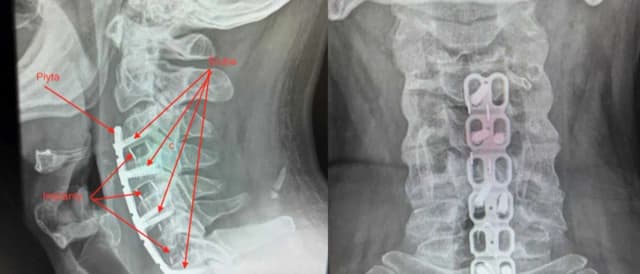

Poznaj objawy dyskopatii szyjnej C6-C7, takie jak ból szyi, osłabienie mięśni i drętwienie. Dowiedz się, jak skutecznie leczyć i zapobiegać tym dolegliwościom.